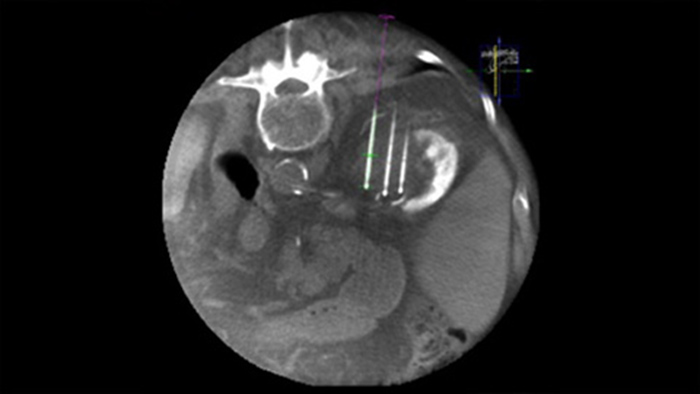

XperGuide Ablation* bietet umfassende Unterstützung bei der Behandlungsplanung und Echtzeit-Nadelnavigation. Die spezielle Parallaxenkorrektur ermöglicht die Planung von Nadelverläufen bei außermittigen Läsionen.1 Um eine möglichst gute Nadelposition für eine wirksame Ablation zu erreichen, zeigt dieses Tool den virtuellen Nadelverlauf an. Auch die Planung mehrerer Ablationsnadeln wird dadurch unterstützt. Außerdem werden Nadeleigenschaften wie Ablationszone/Isotherm angezeigt, damit die vollständige Tumorabdeckung vor der Ablation verifiziert werden kann.

XperGuide bietet eine besonders präzise Live-Bildführung für jede Nadel zur Zielposition. Hierfür wird das Durchleuchtungsbild mit den vorab geplanten Bewegungsverläufen überlagert.3

Mithilfe eines nach der Ablation erfassten CBCT-Bilds können Sie die Tumorabdeckung und damit die Vollständigkeit der Behandlung verifizieren.